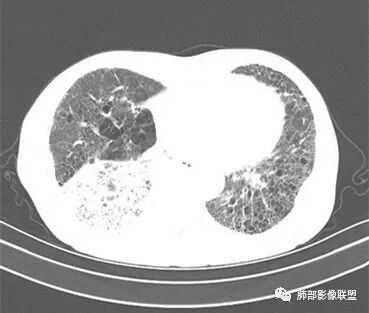

双肺慢支肺气肿。右肺下叶大片状影,支气管狭窄,枯枝状。间杂网格状影,实变影(与胸膜糊墙),叶间裂膨隆。右肺门增大。增强后右下肺片状影内血管束失去正常形态,边缘模糊。实变影不均匀强化。纵隔及右肺门多组淋巴结肿大,其中右侧10、11、12组淋巴结肿大内见液化。考虑肺炎型肺癌并感染?不典型结核待除外。左下小片影?(层面不全)。

右肺下叶大团块影,斜裂膨隆,内支气管破坏,纵隔窗实质性成份少有强化(假大空),肿瘤CA125、199高,考虑粘液腺Ca右肺门淋巴结及纵隔淋巴结大,右肺下动干起始处充盈缺损(示栓塞或Ca栓;余肺叶弥散网格状改变,间质增厚及纤维化表现!

老年男性的病人。慢性的咳嗽憋喘为主的症状,慢性的病程。临床ca199明显的增高,癌胚抗原升高。白细胞增高提示有肺部感染的。影像学表现两肺弥漫性的网格状改变。而病变又集中在右肺下叶。右肺门见一个大结节的病灶,内部有片状坏死,不均匀的强化,邻近的支气管变窄,周围的肺组织呈大片状的实变影。纵隔淋巴结多个肿大。这样的影像学考虑右侧肺门旁的恶性病变。鳞癌或者粘液性腺癌,伴纵隔淋巴结转移,右肺下叶的癌性淋巴管炎,两肺慢性的间质性肺炎。

老年男性,反复咳嗽咳痰喘憋8年,加重10天,发热半天。白细胞计数明显升高(存在细菌感染可能),CEA、CA19—9升高(肺癌或间质性肺疾病引起可能)。痰培养见肺克。CT;双肺弥漫小叶间质、中轴间质增厚,胸膜下肺气肿,右肺门及右下叶可见实变影,边界模糊,内支气管走形僵硬,部分见蜂窝样改变,增强后实变区可见低密度区(粘液?),叶间裂膨隆,纵隔及右肺门见肿大淋巴结,右肺门淋巴结内见坏死。存在感染,但单纯感染难以解释支气管走行僵硬、实变内的低密度病灶,考虑恶性伴感染,肺炎性肺癌或黏液腺癌。

病史八年,慢支病史,两肺中轴间质及小叶间隔增厚,可见胸膜下线,提示有间质性肺病ulp,右下肺大片实变,叶间裂膨隆,纵隔淋巴结肿大,实变内GGO以网挌为中心,强化有血管造影征,实变内支气管走行僵直〈枯树枝征)并扭曲扩张,可见低密度粘液拴,综合考虑为1,右下肺炎性肺癌,粘液腺癌可能性大,2,uip

2.影像表现:肺气肿背景,右肺下叶呈现明显网格影及蜂窝影、枯枝征,边缘膨隆、叶间裂向前方推移。病灶密度不均,前份见不规则片状实性密度区,实性部分轻度强化,边界不清,周边特征掩盖不清。支气管主要分支显示,呈枯枝征。纵隔窗病灶密度偏低,病灶内血管影边缘稍显模糊,未见明显液化坏死区。

余双肺未见明显结节影。

右侧肺门淋巴结肿大,中央低密度;纵隔见轻度增大淋巴结。